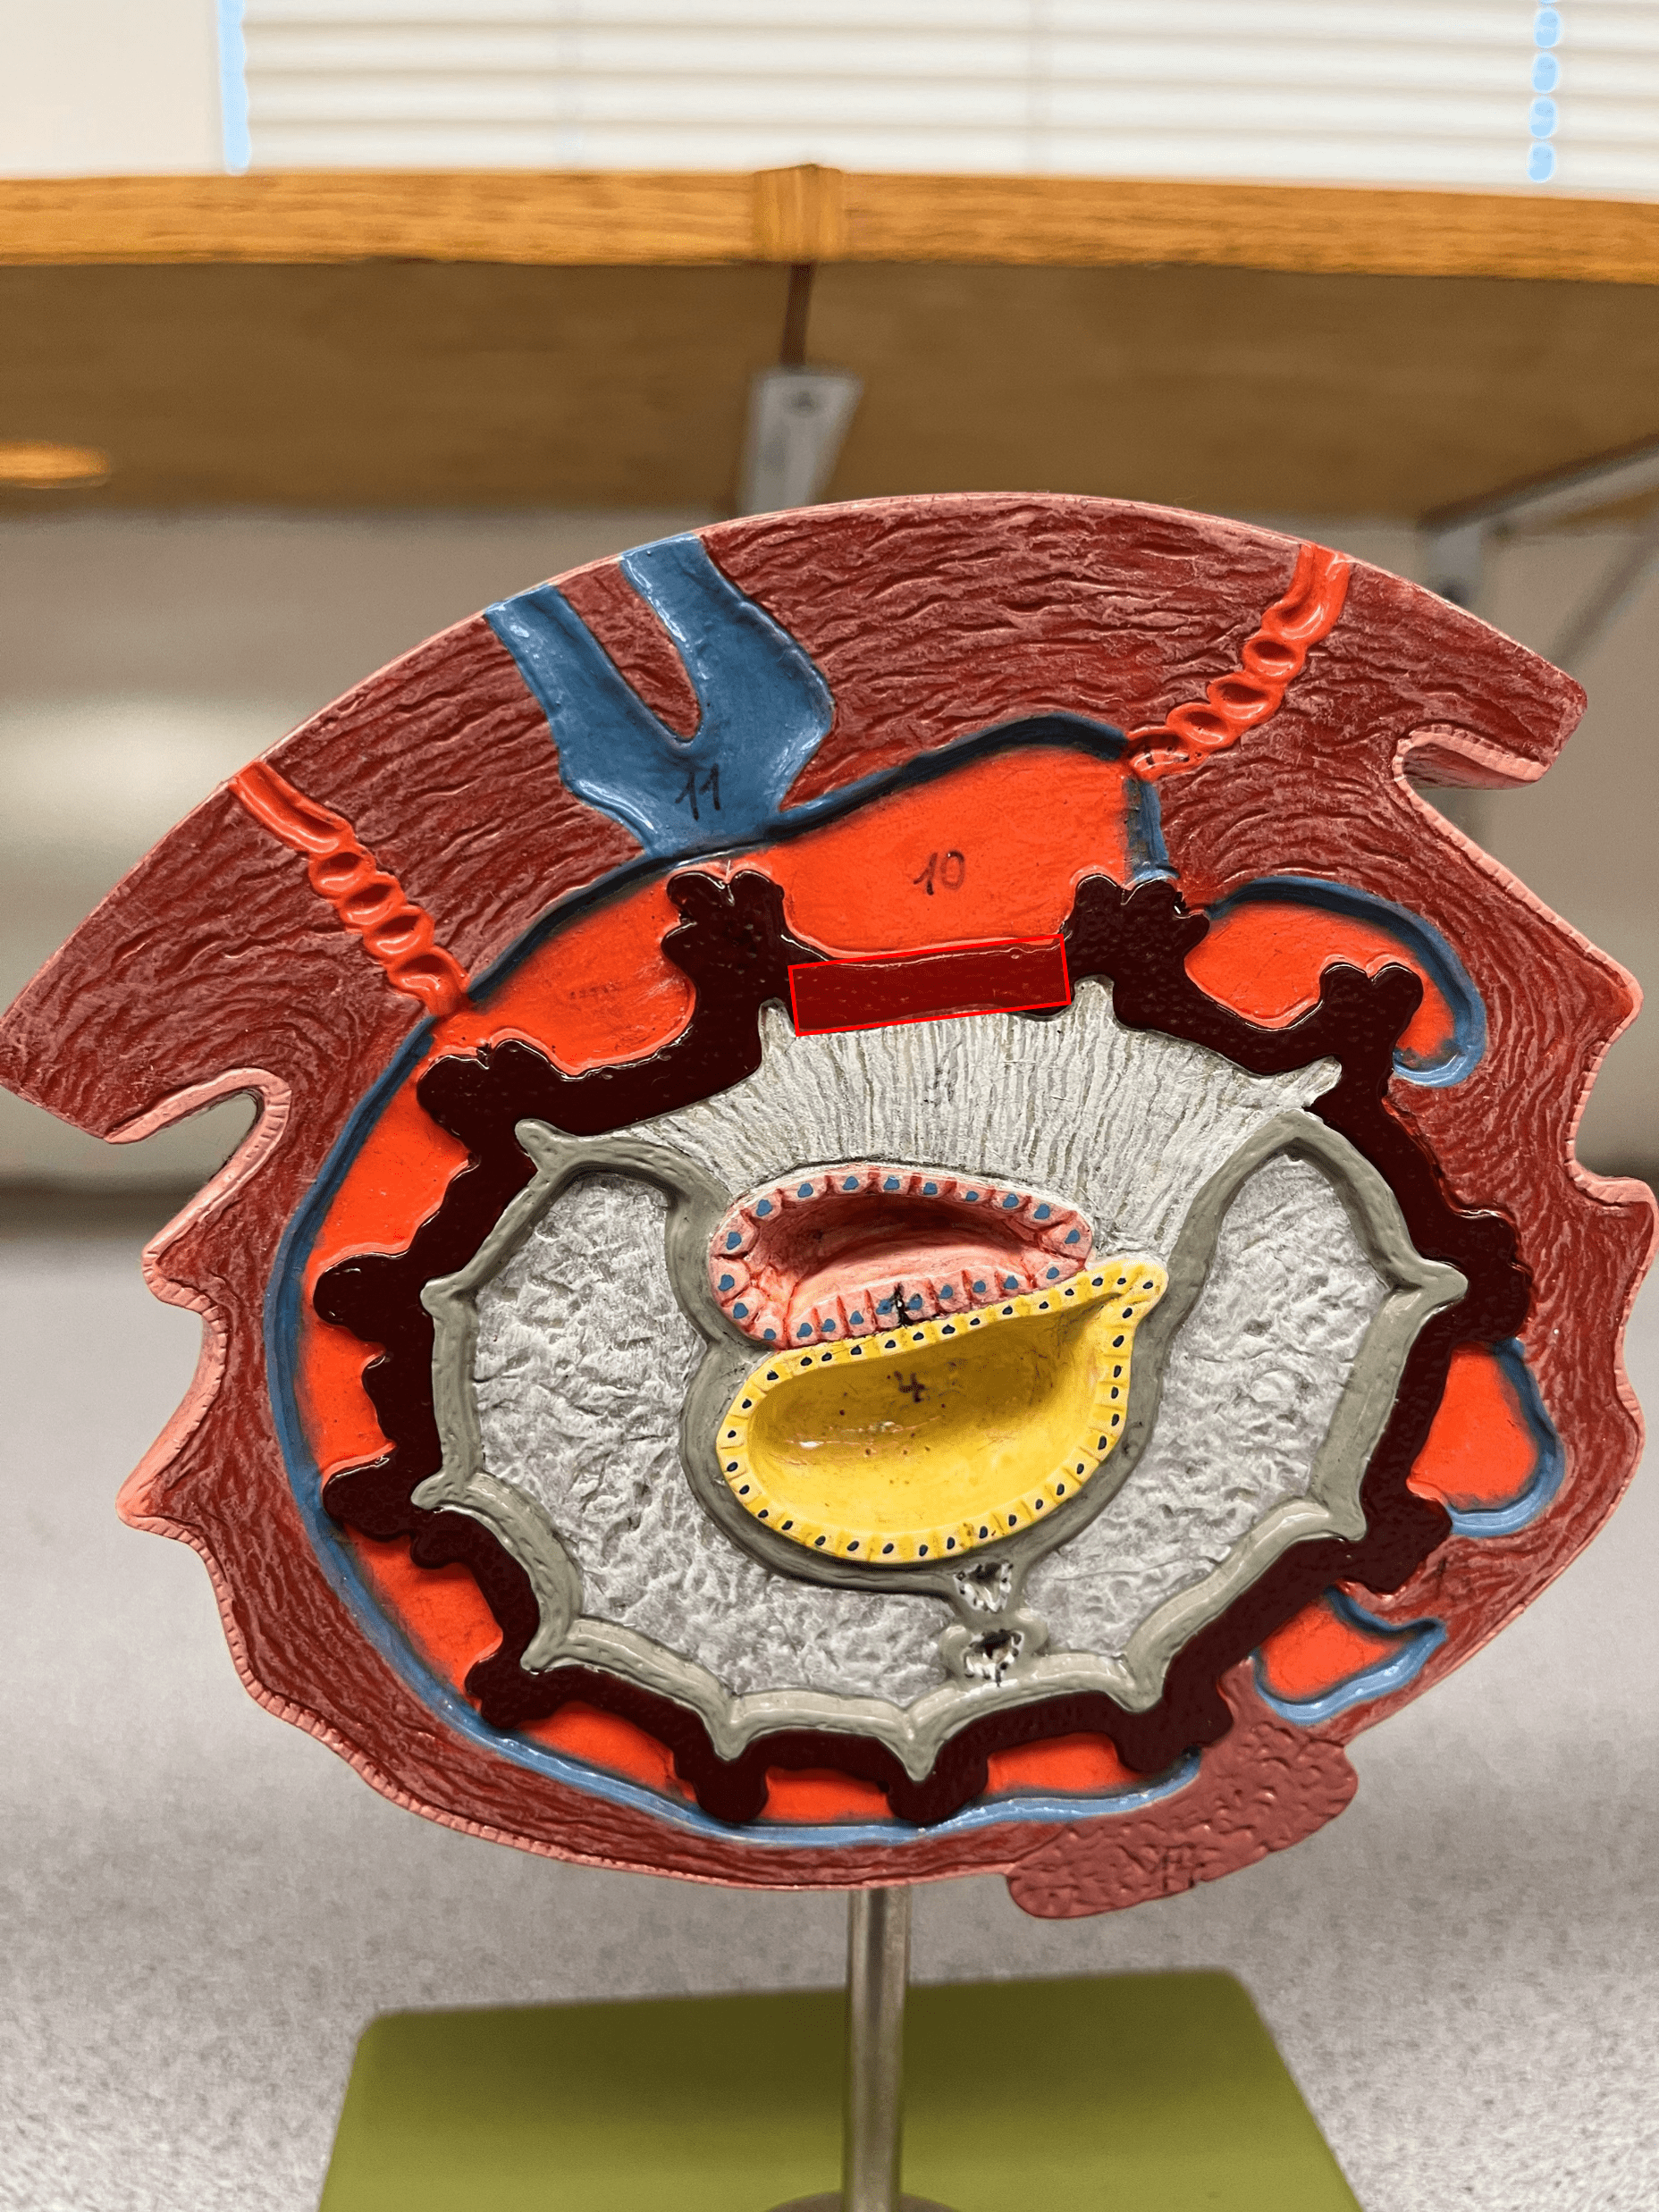

• Model of the 15-day embryo.

• Faces the amniotic cavity.

• Model of the 15-day embryo.

• Faces the yolk sac.

• Model of the 15-day embryo.

• Forms the inner sac around the embryo and is filled with amniotic fluid.

• Model of the 15-day embryo.

• Filled with amniotic fluid.

• Model of the 15-day embryo.

• Site of early blood formation.

• Model of the 15-day embryo.

• A small projection of the yolk sac.

• Forms part of the umbilical cord and part of the urinary bladder.

• Model of the 15-day embryo.

• Forms the outermost membrane around the fetus and embryonic portion of the placenta.